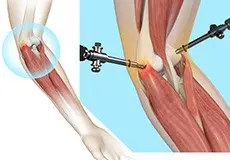

Elbow Arthroscopy

Elbow arthroscopy, also referred to as keyhole or minimally invasive surgery, is a surgical procedure performed through tiny incisions